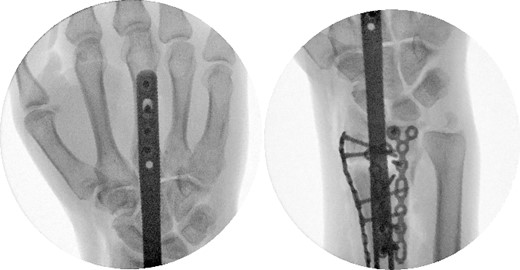

Two weeks following the procedure, the patient returned to the clinic for a follow-up visit. The wrist was swollen and ROM was limited. Hand motor functions and neurovascular exam were fully intact. Radiographs taken in clinic showed intact hardware with healing fracture. At 2 months follow-up, radiographs showed intact hardware with interval bone bridging across fracture sites. Radiographic parameters including articular alignment, radial height, radial inclination, and volar tilt were in acceptable ranges (Fig. 5). The patient reported no concerns or complications. A computed tomography (CT) scan was obtained at 10 weeks after the procedure and confirmed adequate bony healing and alignment without failure (Fig. 6). The dorsal spanning plate was eventually removed 1 month later and 4 months since the initial operation (Fig. 7).

Radiological assessment at 2 months postprocedure with PA and lateral views.